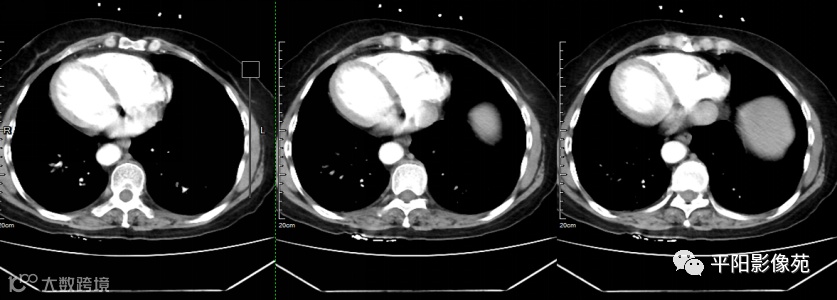

影像检查

完全内脏转位是指心脏、肺部、横膈及腹腔脏器等全部内脏呈180°转位,因此又被称为“镜面人”,其发生率0.5/10 000~2/10 000。